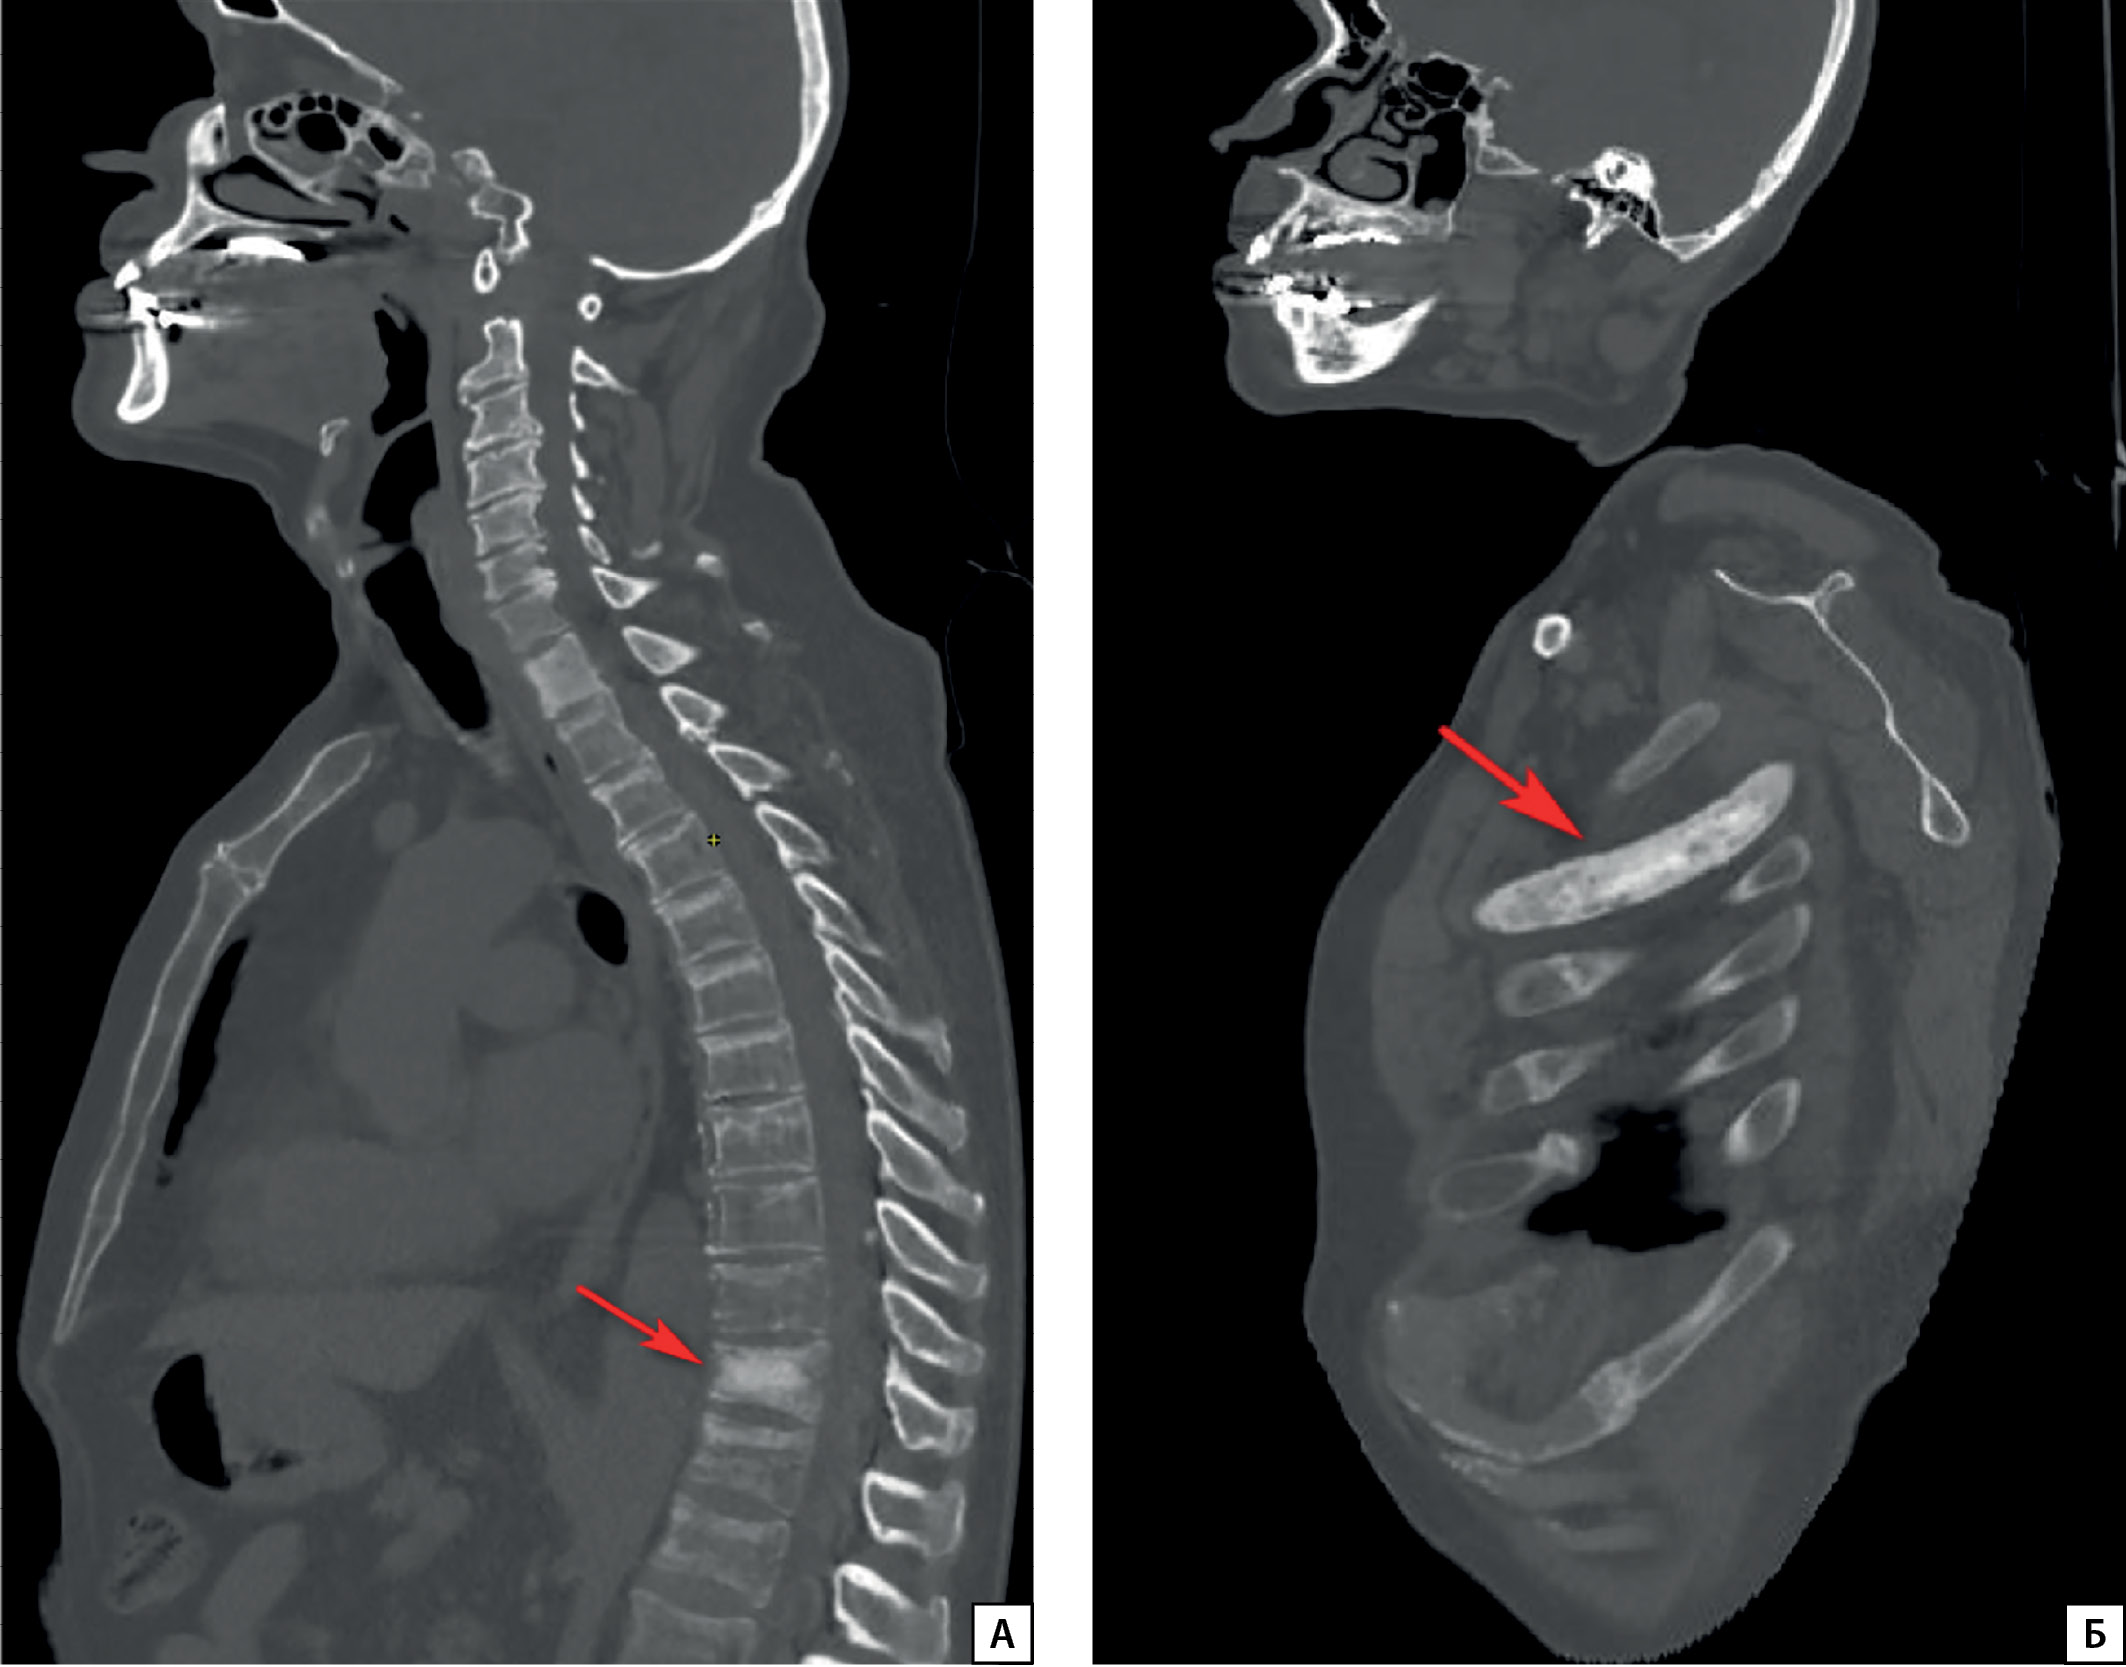

Рисунок 3.1. Результаты ОФЭКТ/КТ пациента П.

Описание: в левой половине тела с распространением на ножку дуги Th11 позвонка визуализируется очаг остеосклероза с ровными контурами, размерами 43×22×22 мм, с повышенной фиксацией РФП (стрелки) во фронтальной (А), сагиттальной (Б), аксиальной (В, Г) плоскостях.

Для топической диагностики проведена соматостатин-рецепторная сцинтиграфия в режиме «все тело» с 99mTc-тектротидом. Отмечается гиперфиксация радиофармацевтического препарата в очагах пораженных костей (рис. 3.1, 3.2), что свидетельствует о наличии соматостатиновых рецепторов в этих участках, и, наиболее вероятно, метастатическое поражение является источником продукции ФРФ23.

Поиск ФРФ23-образований выполняют поэтапно. Вначале проводят «функциональную визуализацию», т.е. используют специфические радиофармпрепараты (РФП), которые накапливаются в ткани опухоли за счет наличия в ней соматостатиновых рецепторов 2А подтипа [27]. Применяется сцинтиграфия с РФП (99mTc-тектротид, 111In-октреотид) либо позитронно-эмиссионная томография с РФП (соли галлия: 68Ga DOTA-TATE/NOC). Затем осуществляют топический поиск опухоли: КТ, МРТ, УЗИ. При таком подходе удается верифицировать до 70% образований [28]. У пациента П. были обнаружены множественные очаги с гиперфиксацией РФП в очагах пораженных костей, что свидетельствует о наличии в метастазах соматостатиновых рецепторов,а значит, косвенно подтверждает секрецию ФРФ23.